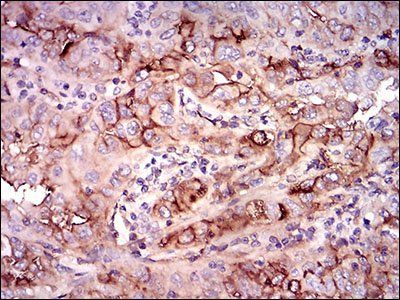

IHC staining of FFPE human prostate carcinoma with CD73 antibody (clone NT5E/2545). HIER: boil tissue sections in pH9 10mM Tris with 1mM EDTA for 10-20 min and allow to cool before testing.

IHC staining of FFPE human pancreatic carcinoma with CD73 antibody (clone NT5E/2545). HIER: boil tissue sections in pH9 10mM Tris with 1mM EDTA for 10-20 min and allow to cool before testing.